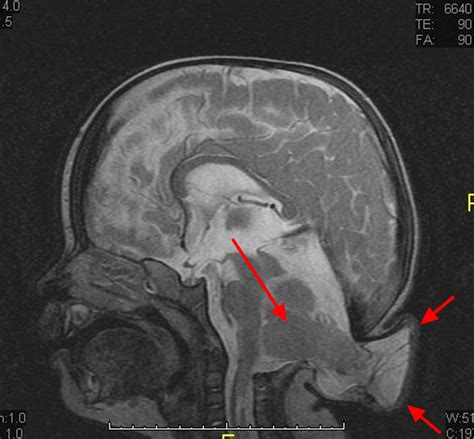

Receiving a diagnosis of Chiari malformation can be an overwhelming experience, often accompanied by a flurry of questions regarding long-term health and quality of life. This condition, which occurs when the lower part of the brain—the cerebellum—extends into the spinal canal, can cause a wide range of debilitating symptoms, including chronic headaches, neck pain, balance issues, and neurological deficits. Fortunately, medical advancements have paved the way for diverse Chiari malformation treatments that aim to relieve pressure on the brain and spinal cord, stop the progression of neurological damage, and improve overall patient function.

The severity of the condition often dictates the strategy. If left untreated, severe cases can lead to syringomyelia (the development of a fluid-filled cyst within the spinal cord), which significantly heightens the risk of permanent nerve damage. Therefore, timely diagnosis and professional evaluation are critical.

When conservative methods fail or when the anatomy presents a clear threat to neurological health, surgical intervention becomes the primary path. The most common and effective of the Chiari malformation treatments is a procedure known as posterior fossa decompression. The goal of this surgery is to create more space for the cerebellum and allow for the normal flow of cerebrospinal fluid (CSF).

During a typical decompression surgery, the surgeon removes a small piece of bone from the base of the skull and sometimes a small part of the top of the spinal canal. Often, the surgeon will also open the dura mater (the thick covering over the brain) and sew in a graft to enlarge the space, a process called duraplasty. This is considered the gold standard among Chiari malformation treatments because it directly addresses the cause of the compression.